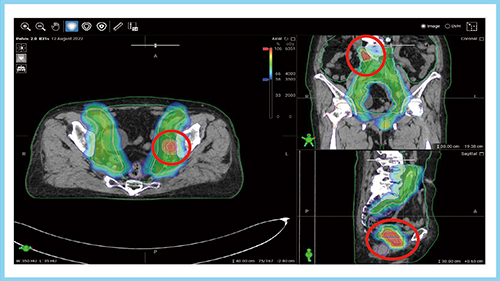

最適化・線量計算時間は,固定多門IMRTでは7門,9門,12門いずれも約120〜140秒と,門数による大きな違いは見られなかった。VMATもarc数による違いは小さかったが,線量計算時間は固定多門IMRTの約3倍であった。また,図1はそれぞれの線量分布図で,いずれの照射法も当院の線量評価指標を満たしていた。以上から,治療時間を考慮すると,固定7門のIMRTが最適なビーム配置と考えた。

図1 5つの照射法による線量分布図